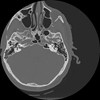

7 HUESO,,Vol,0.5,HUESO,,